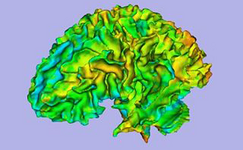

Arctic wizard (Automatic Regional Cortical ThICkness)